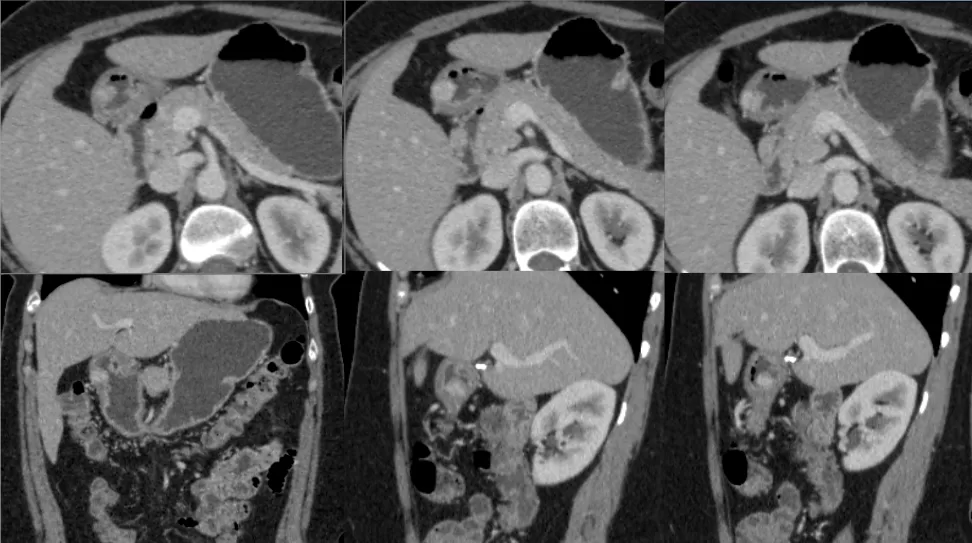

• Mulher de 40 anos

• Hipertensão, tabagismo, hipotireoidismo

• Dor abdominal difusa e intermitente, com duração de 3 meses

• Colecistectomia laparoscópica: 7 anos atrás

Cálculos biliares aderidos à parede duodenal

Colelitíase Livre na Cavidade Abdominal

-> Litíase aderida à parede duodenal: apenas alguns casos relatados na literatura